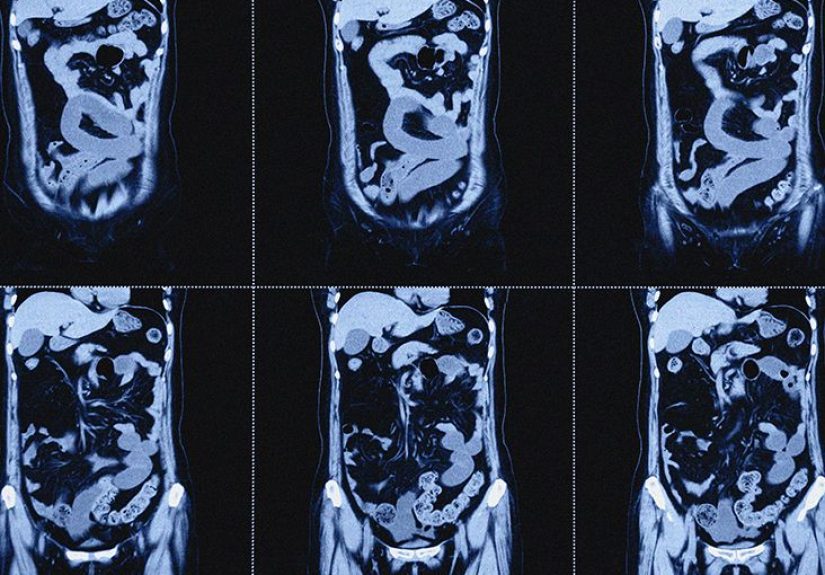

How do intestines fit inside your body without turning you into a human pretzel?

Your intestines fit for two big reasons: folding and flexibility.

The small intestine forms loops and coils, suspended by a thin sheet of tissue called the mesentery (which also carries

blood vessels and nerves). The large intestine forms a broader loop around it.